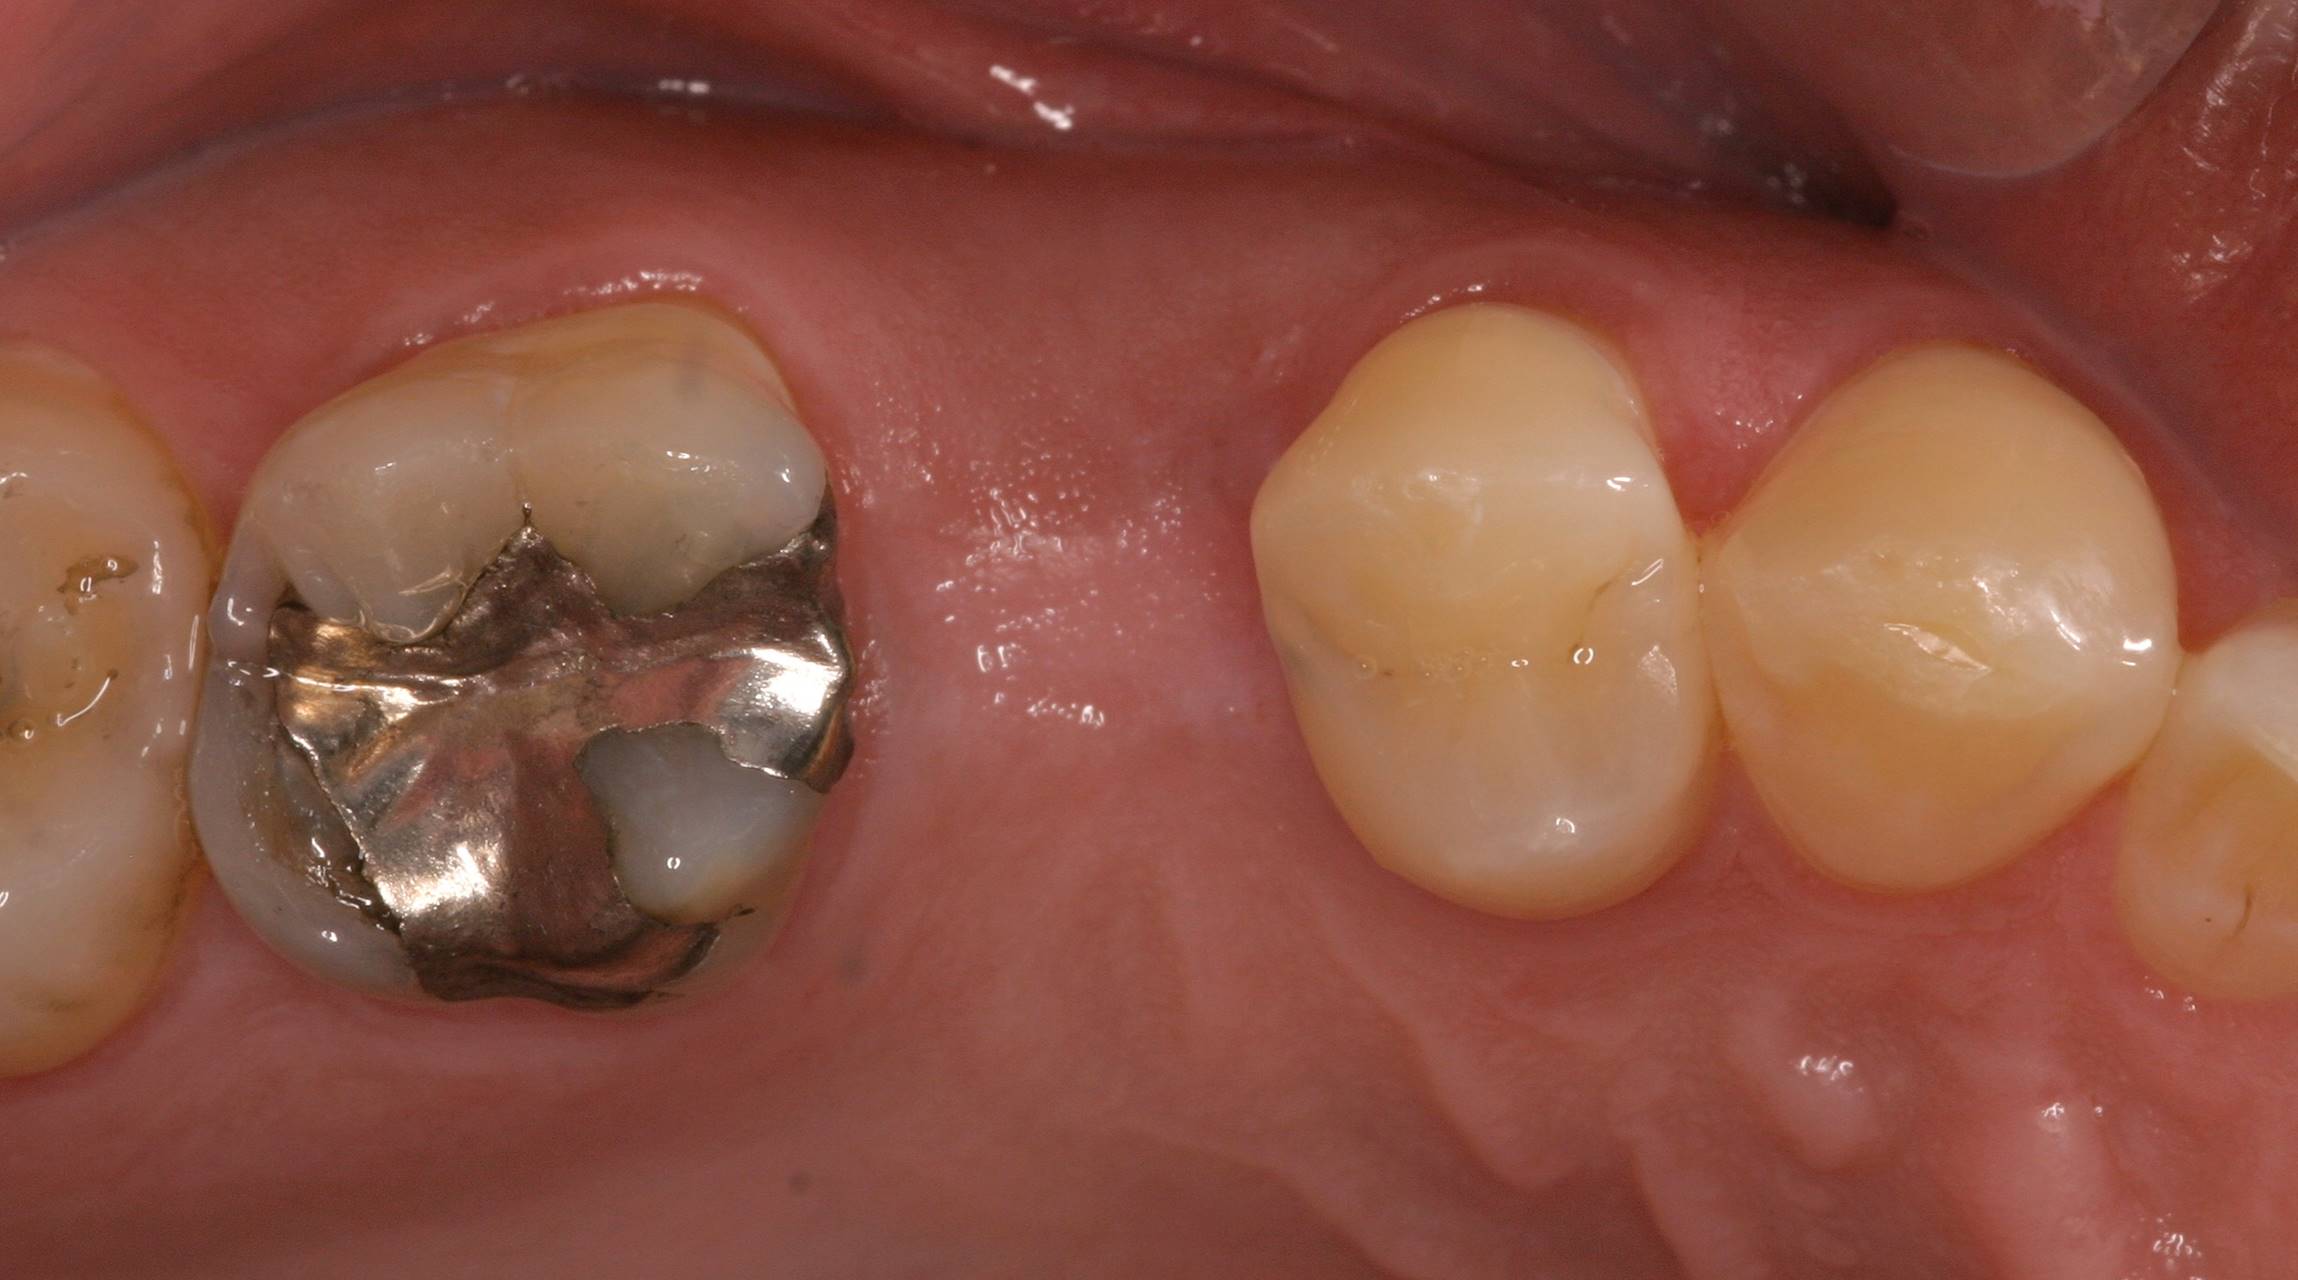

Figure 1. Preoperative occlusal view of a 35-year-old man missing his second premolar, which would be replaced with an implant and screw-retained abutment/restoration.

Figure 1

Figure 9. In the presence of angulation problems or implants placed in the wrong location, cement-retained restorations are often required.

Figure 9